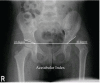

Figure 2

Pelvis X-Ray (AP view) showing left sided dysplastic hip with an increased acetabular index.